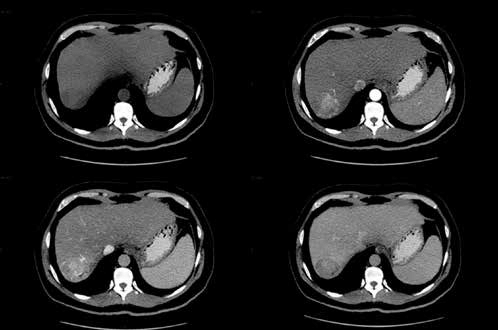

17

Q

metastase hepatica na tc

A

TC axial aprimorada pelo contraste demonstra múltiplas lesões hepáticas hipodensas de tamanhos variados com borda periférica (aparência targetoid